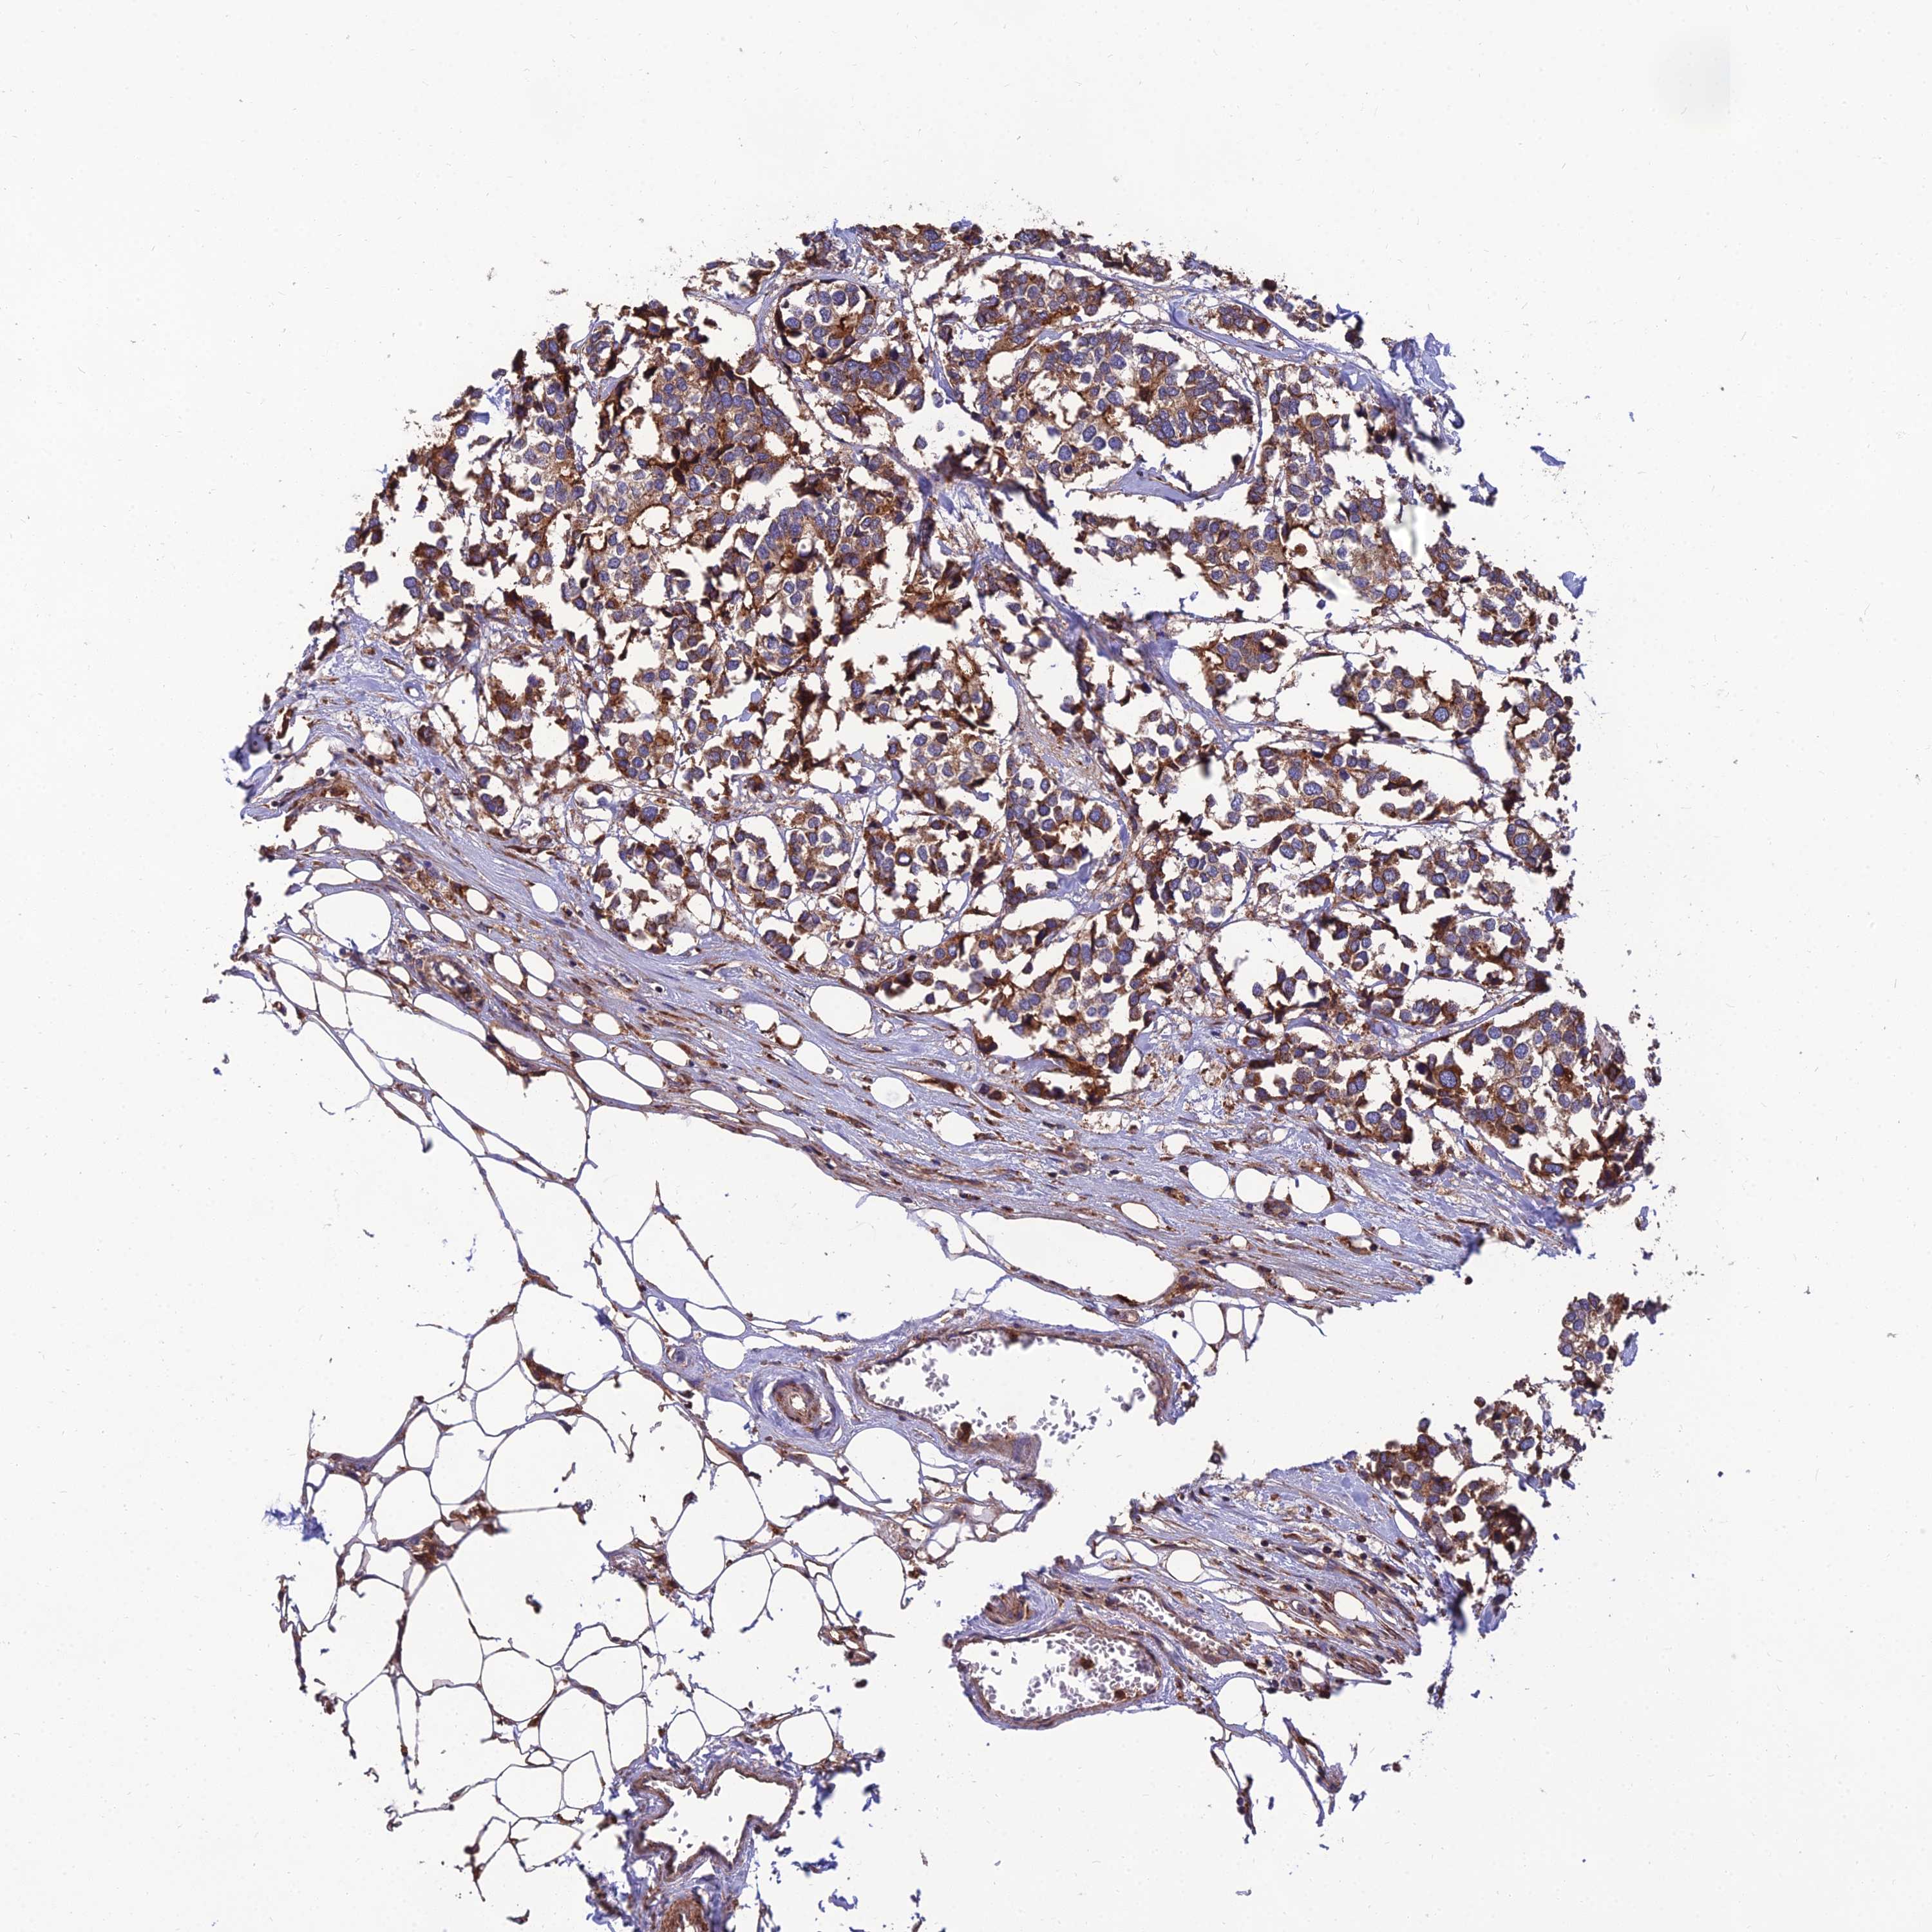

BRCA TCGA BRCA VALIDATION PROTEIN EXPRESSION

ANTIBODIES

AND

VALIDATION